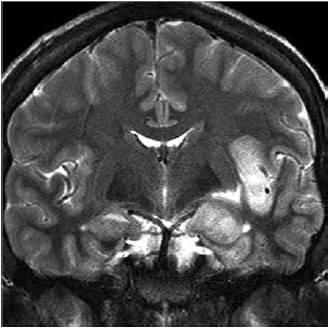

Homem de 63 anos com histórico de hipertensão, tabagismo (30 maços-ano) e etilismo é internado com febre e convulsões de início recente. Ele apresenta espasmos faciais, tremores nos braços e pernas e alguns episódios de tremores aparentemente generalizados que duram 1 hora. Ele recebe o total de 20 mg de diazepam intravenoso, o que interrompe a atividade convulsiva. Ao chegar na UTI, o estado mental começa a piorar e ele é intubado e colocado em ventilação mecânica. A ressonância magnética (coronal, T2) realizada é mostrada a seguir.

(Arquivo pessoal: imagem usada com autorização.)